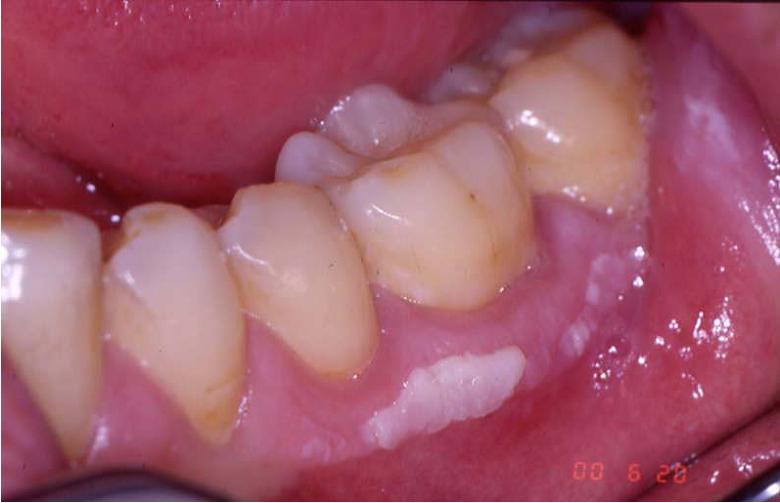

Leukoplakia Oral Cancer White Spots On Gums Feb 15 2024 nbsp 0183 32 Leukoplakia loo koh PLAY key uh causes thick white patches that form on the gums The patches also may form on the insides of the cheeks and the bottom of the mouth

Jan 25 2023 nbsp 0183 32 Oral leukoplakia presents as white plaques of questionable risk diagnosed when other known diseases or disorders that carry no risk for oral cancer have been excluded Leukoplakia is a predominantly white lesion of the oral mucosa than cannot be clinicopathologically characterized as any other definable lesion The term leukoplakia is a

Jul 17 2023 nbsp 0183 32 Oral leukoplakia is a white patch or plaque that develops in the oral cavity and is strongly associated with smoking Risk factors include all forms of tobacco use forms including Nov 8 2023 nbsp 0183 32 Leukoplakia or white and gray patches inside the mouth may be caused by irritation Or the condition may be a sign of oral cancer Learn more about how leukoplakia is